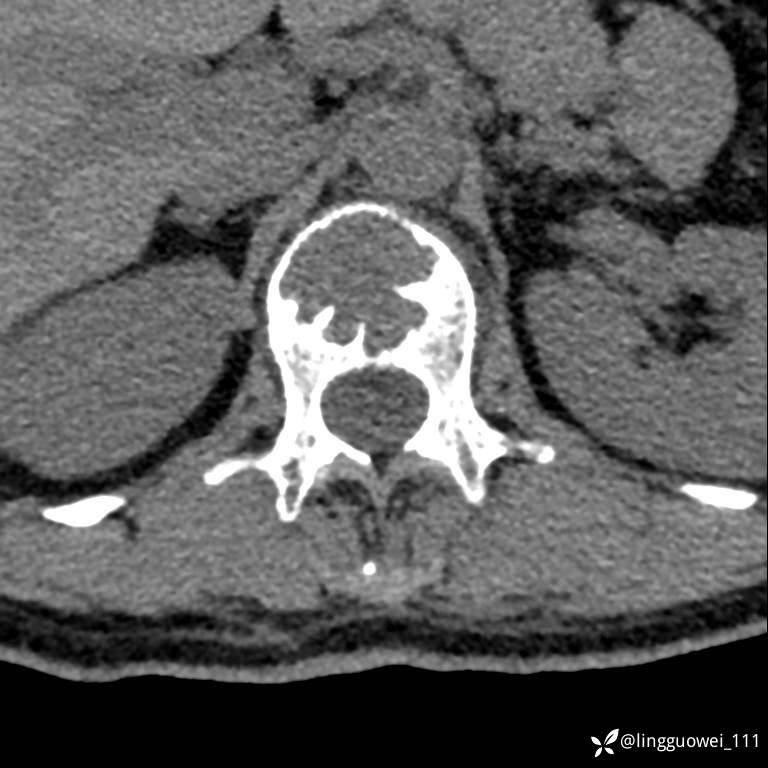

病例女,39岁,腰痛来诊,只有CT可能要鉴别诊断,而MR可以定性吗?

患者性别:女

患者年龄:39岁

主诉:腰痛